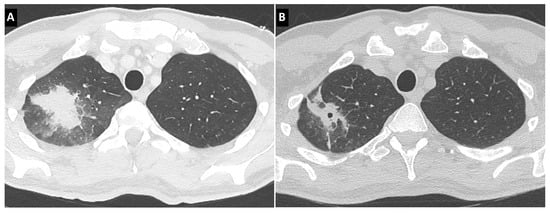

- Greene, R.E.; Schlamm, H.T.; Oestmann, J.-W.; Stark, P.; Durand, C.; Lortholary, O.; Wingard, J.R.; Herbrecht, R.; Ribaud, P.; Patterson, T.F.; et al. Imaging findings in acute invasive pulmonary aspergillosis: Clinical significance of the halo sign. Clin. Infect. Dis. 2007, 44, 373–379. [Google Scholar] [CrossRef]

- Prasad, A.; Agarwal, K.; Deepak, D.; Atwal, S.S. Pulmonary aspergillosis: What CT can offer before it is too late! J. Clin. Diagn. Res. 2016, 10, TE01–TE05. [Google Scholar] [CrossRef]

- Munoz, P.; Vena, A.; Cerón, I.; Valerio, M.; Palomo, J.; Guinea, J.; Escribano, P.; Martínez-Sellés, M.; Bouza, E.; Promulga Project Group. Invasive pulmonary aspergillosis in heart transplant recipients: Two radiologic patterns with a different prognosis. J. Heart Lung Transplant. 2014, 33, 1034–1040. [Google Scholar] [CrossRef]

- Herbrecht, R.; Guffroy, B.; Danion, F.; Venkatasamy, A.; Simand, C.; LeDoux, M.-P. Validation by real-life data of the new radiological criteria of the revised and updated consensus definition for invasive fungal diseases. Clin. Infect. Dis. 2020, 71, 2773–2774. [Google Scholar] [CrossRef]